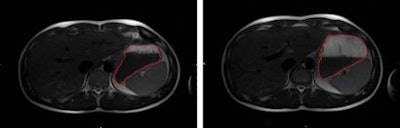

The MRI scans showed that drinking the large glass of water doubled the stomach content compared to the smaller glass. In addition, subjects reported feeling fuller and less hungry after drinking the larger amount of water. Lead author Guido Camps and colleagues also found that brain activation increased with greater distention of the stomach.

Based on their findings, the group concluded that adding water increases distension of the stomach, while also increasing regional brain activity and curbing short-term appetite.